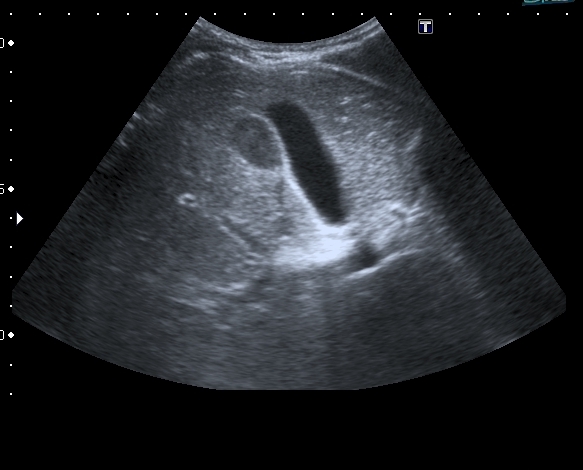

Порекомендовал КТ, но в связи с наступающими новогодними праздниками и каникулами мальчик уехал домой и появился повторно через 2 месяца без жалоб для контрольного исследования. На УЗИ - картина осталась без динамики

Предположил наличие удвоения желчного пузыря, с этим заключением пациент исчез из поля зрения.